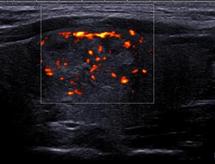

Le doppler énergie permet de rechercher une hyperhémie synoviale le plus souvent liée à une activité inflammatoire.

Contrairement au doppler couleur et au doppler pulsé, la technique ne dépend pas de l’angle de tir, c'est-à-dire de l’inclinaison de la sonde. Par contre, pour ne pas avoir d’artefacts de mouvement, il vous faudra immobiliser parfaitement le patient et la sonde, ce qui n’est pas si simple à faire !

Autre problème de taille: le signal doppler est plus ou moins sensible en fonction des appareils des constructeurs.

Enfin, il n’est pas non plus évident d’évaluer l’importance de l’inflammation en se référant à l’intensité du signal.

a) Régler la PRF (Pulse Repetition Frequence) autour de 1000 Hz pour l’échographie de l’appareil locomoteur

b) Augmenter progressivement le gain jusqu’à voir apparaître un signal en regard des corticales osseuses

c) Si vous observez un signal dans un tissu synovial avant qu’il n’apparaisse sur la corticale osseuse, vous pouvez conclure à une hyperhémie et donc à l’inflammation de ce tissu synovial.